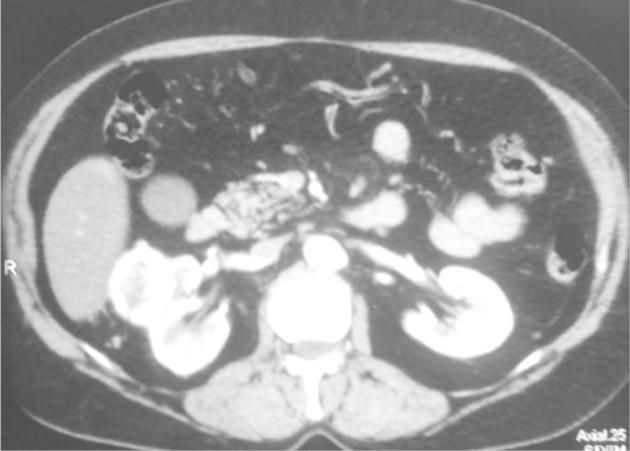

The association of renal cancer and renal tuberculosis is uncommon. While the incidental discovery of renal cell carcinoma in a tuberculous kidney is a classical finding, the discovery of tuberculous lesions after nephrectomy for cancer is exceptional. We report the case of a female patient aged 60 who had a partial nephrectomy for a 5 cm exophytic kidney tumor. Pathological examination concluded that renal clear cell carcinoma associated with follicular caseo tuberculosis.

肾癌与肾结核的关联并不常见。虽然在结核性肾脏中偶然发现肾细胞癌是一个经典发现,但在因癌症进行肾切除术后发现结核病变则较为罕见。我们报告一例60岁女性患者,因一个5厘米的外生性肾肿瘤接受了部分肾切除术。病理检查结果为肾透明细胞癌合并滤泡性干酪样结核。